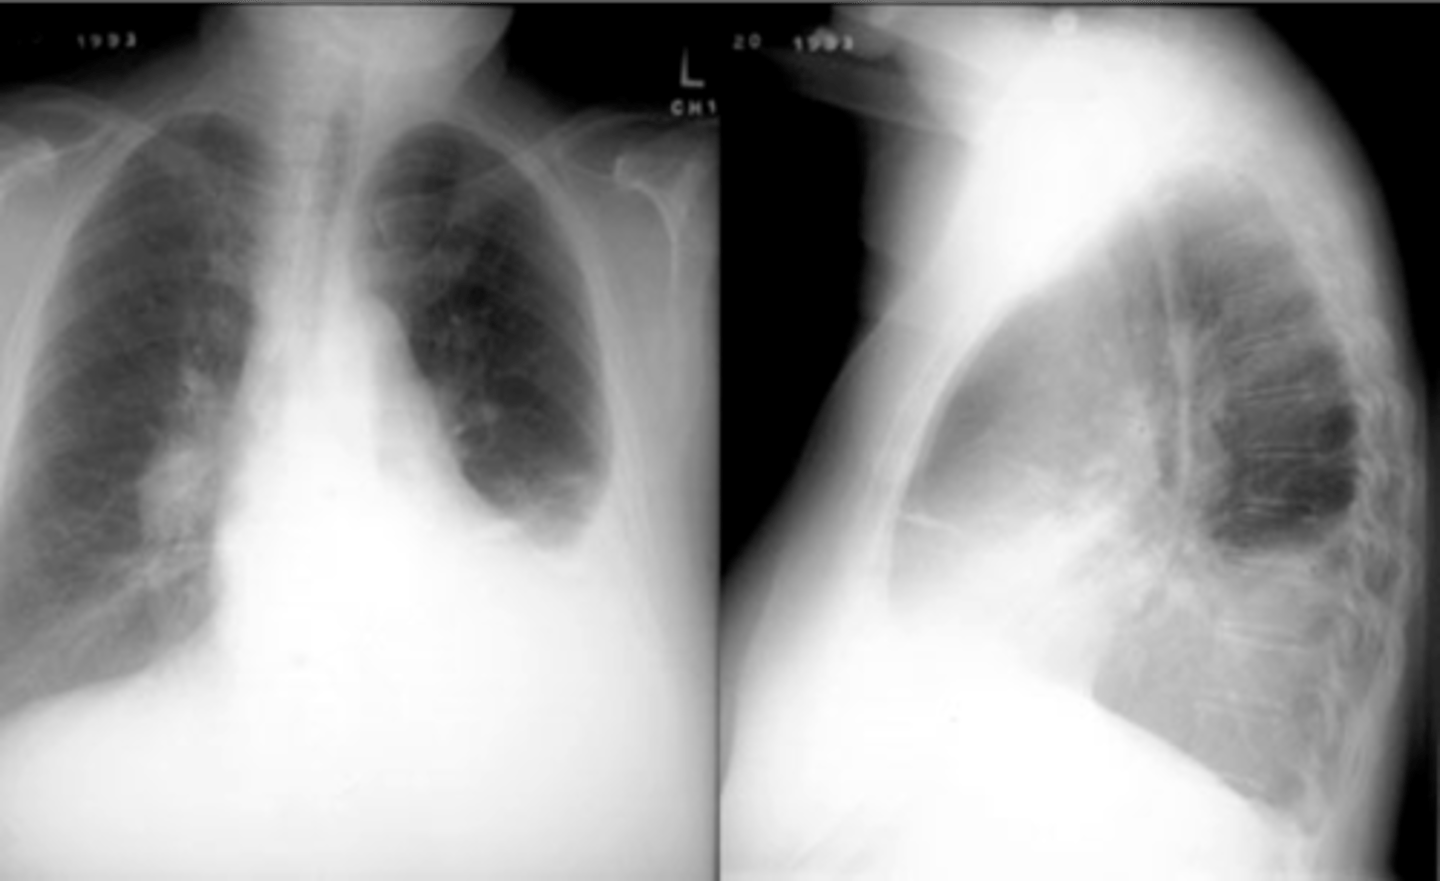

RUL bullae

Flattening of hemidiaphragms

& blunting of costophrenic angles, Increased AP diameter (barrel chest), bullae or large air cavities indicates

hyperinflation

COPD/Emphysema

COPD/Emphysema

Bullae RUL